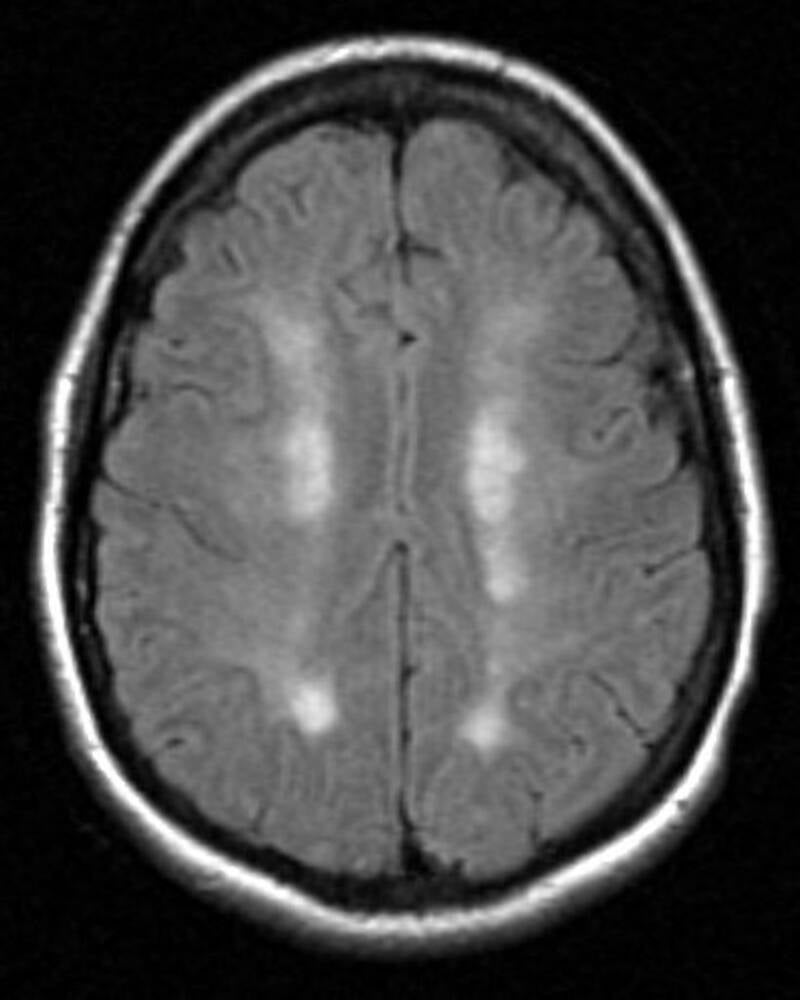

Typisch patroon op de scans

Op de scans is vaak een 'rozenkrans'-patroon te herkennen; een langwerpig patroon. Zie onderstaande afbeeldingen:

Case courtesy of A.Prof Frank Gaillard, Radiopaedia.org. From the case rID: 2626 and the case rID: 5199